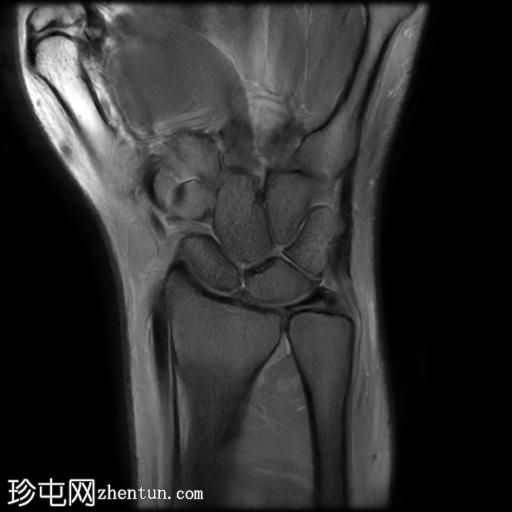

冠状面

T2

T1

MRI显示腕部第一背侧肌腱(拇长展肌和拇短伸肌)增厚,并伴有异常增厚的实质内液体信号。腱鞘内液体增多。

尺侧腕伸肌腱可见异常线性实质内液体信号增多,与板状间质撕裂相关。

MRI表现和临床表现提示De Quervain腱鞘炎。